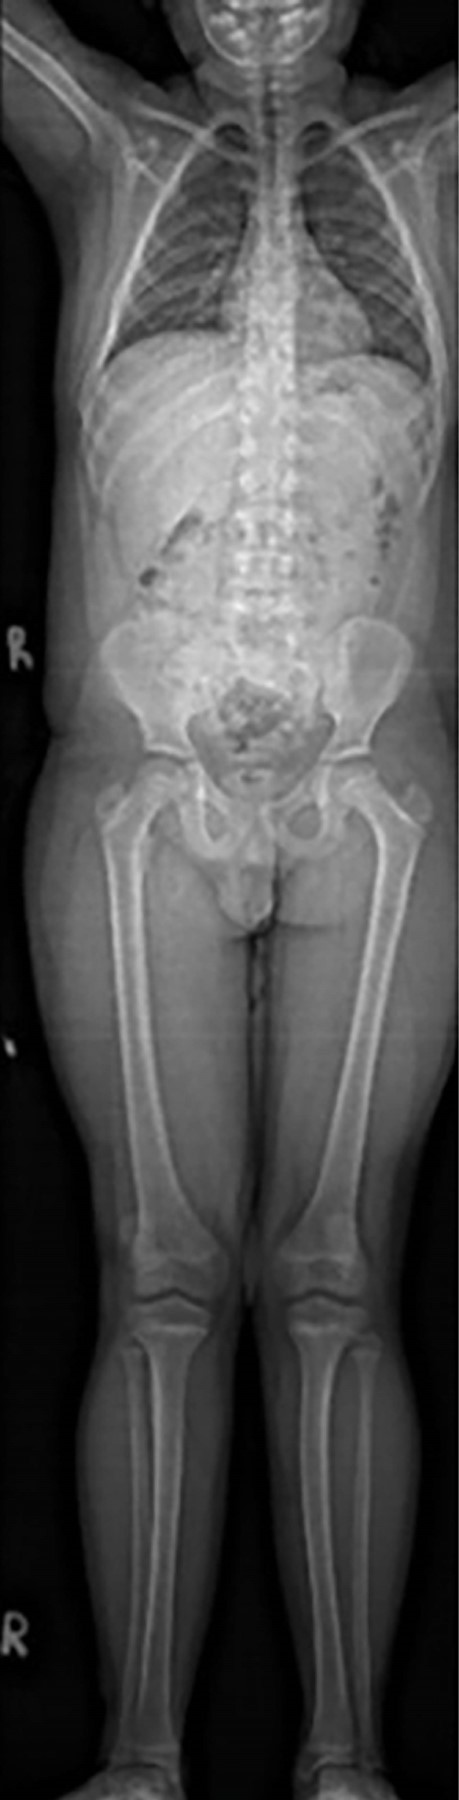

En las radiografías simples de columna toracolumbar no se observaron signos de escoliosis (Figura 4).